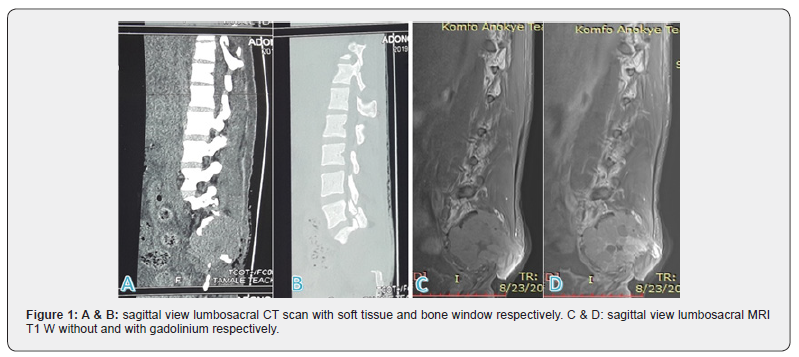

Lumbosacral CT scan showed a heterogenous sacral mass measuring 5.8×6.5×6.2cm with bony distraction of the sacrococcygeal spine (Figures 1A & 1B). Lumbosacral MRI showed a 6.8×7.0×6.8cm lobulated heterogenous T1W hypointense and T2W hyperintense right sided mass involving the vertebral bodies, laminae and pedicles of S1, S2 and S3. The mass extends across the sacroiliac joint and involves the right iliac bone. It encases the right S1-S3 nerve roots with attendant severe canal stenosis. There is also infiltration of the right erector spinatus muscle posteriorly (Figures 1C & 1D).